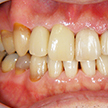

16. セラミック冠セット時右側

4番は抜歯してすでにありませんが2,3,5番にかけて連続性が確保でき、歯列が改善されました。審美的にも清掃面でも良好な環境となったと思われます。

17. セラミック冠セット時左側

反対側から見ても右側歯列の連続性が確保されています。セラミック冠だから「自費でいくら」ではなく、その環境を向上させるための過程の説明や努力、情熱が自費診療なのだと再確認した症例です。この仕事は自由診療費として約50万円強と健康保険処置分の自己負担金で受けました。